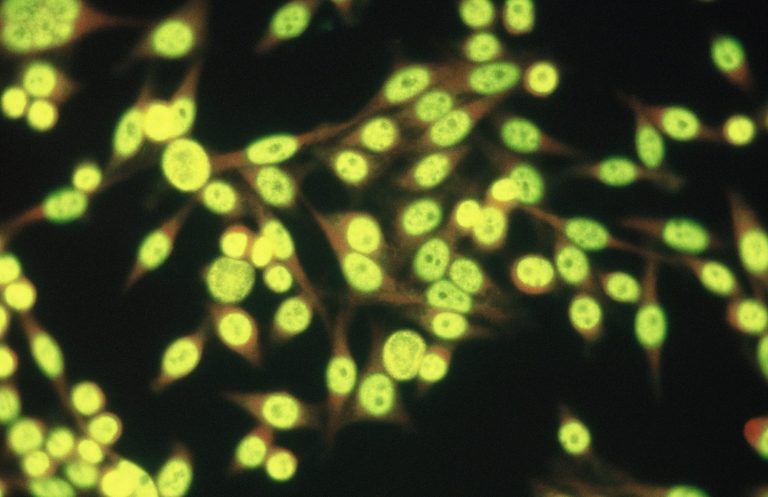

Immunologie

Das Immunsystem kontrolliert die entzündlichen Vorgänge im Körper. Lernen Sie wichtige Bestandteile des Immunsystems kennen